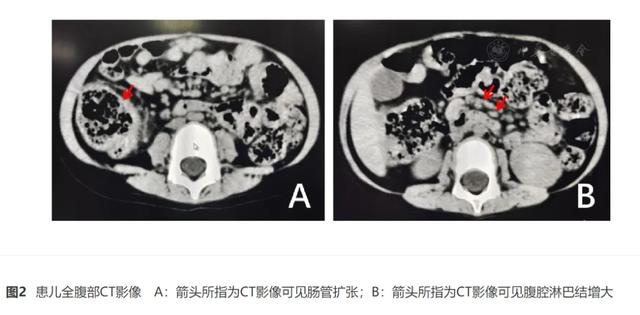

郑州儿童医院风湿科报道的一病例。来源:参考 5

郑州儿童医院风湿科报道的一病例,跟上图同一个病人。来源:参考 5。